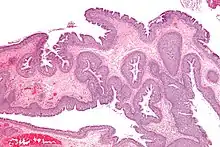

Une endoscopie ou un examen clinique du nez (rhinoscopie) permet le plus souvent de diagnostiquer la PNS. Le scanner des sinus a l’intérêt d'en préciser la topographie. L’examen montre le plus souvent des polypes bilatéraux et congestionnés, accompagnés parfois d’infections. Les polypes ont l’aspect de grappes de raisins blancs. Suivant leur taille ils peuvent gêner la ventilation nasale jusqu'à entrainer une obstruction totale avec blocage de l'écoulement des mucosités, favorisant ainsi la surinfection.